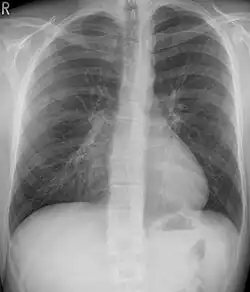

Tension pneumothorax

Tension pneumothorax is an emergent condition in which air gets trapped in the space between the chest wall and the lung. This space is referred to as the pleural space. Because air can't escape from this space, the air pocket grows larger and larger, resulting in the lung collapse closest to the pneumothorax. Forces are transmitted to the mediastinum and effectively "push" the mediastinal structures to the opposite side of the chest.[5]